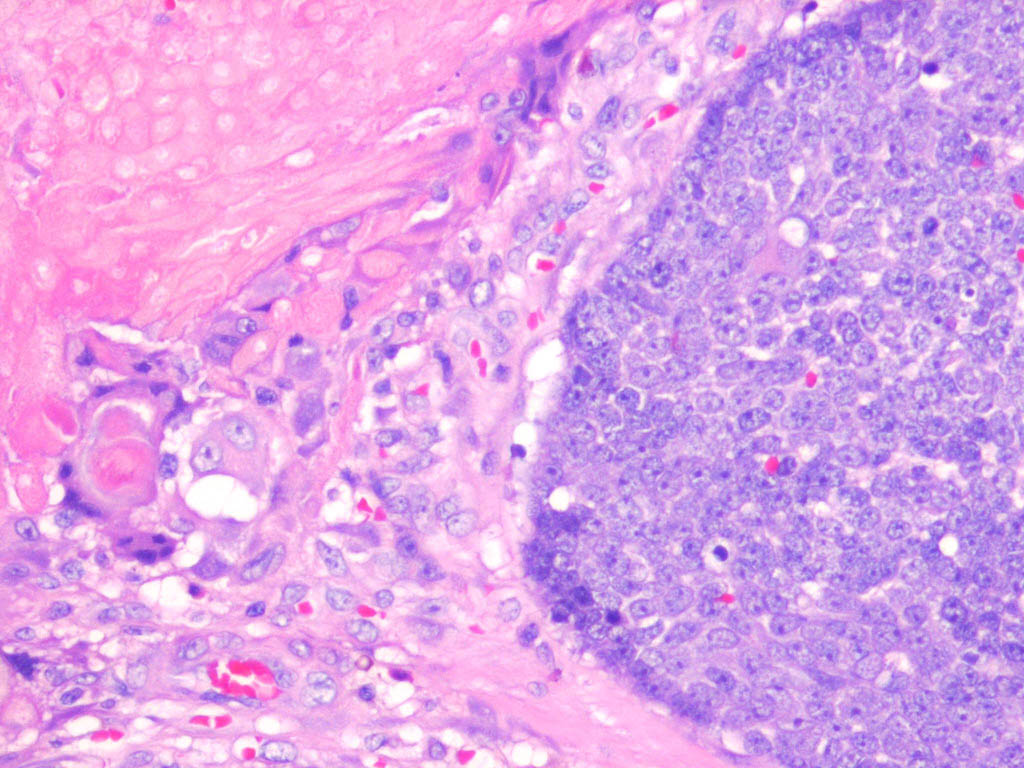

Pilomatricoma shows a spectrum of morphologic features that mainly reflect different evolutionary stages. Early and well-developed pilomatricomas reveal variably sized, round to oval cystic lesions lined by a basaloid epithelium at the periphery and filled in the center with masses of eosinophilic, faulty hair matrix material containing “shadow” (“ghost”) cells

Basaloid (matrical) cells show monomorphous round nuclei with one or more distinctive nucleoli and variable numbers of mitotic figures. Foci of squamoid epithelium are sometimes noted within the epithelial lining. Regressing pilomatricomas display haphazardly arranged foci of basaloid cells and shadow cells as well as an inflammatory infiltrate with multinucleated histiocytic giant cells. Granulation tissue is sometimes noted. Old pilomatricomas reveal no basaloid component but show irregularly shaped, partially confluent masses of shadow cells with foci of calcification or ossification. Melanin deposition, trans-epidermal elimination, and extramedullary hematopoiesis have been described in some pilomatricomas. A peculiar variant with relatively large areas of basaloid cells and small foci of shadow cells (“proliferating pilomatricoma”) is occasionally observed in older adults.